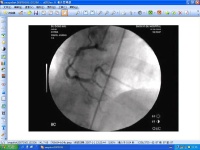

冠状动脉造影是诊断冠心病的一种有效方法。将导管大腿股动脉或其它周围动脉插入,送至升主动脉,然后探寻左或右冠状动脉口插入,注入造影剂,使冠状动脉显影。这样能较明确地揭示冠状动脉的解剖畸形及其阻塞性病变的位置、程度与范围。

虽然心电图等其它检查亦可诊断冠心病,但有时并不准确,最准确的诊断冠心病的方法是冠状动脉造影。冠状动脉造影是目前唯一能直接观察冠状动脉形态的论断方法,医学界号称其为“金标准”。